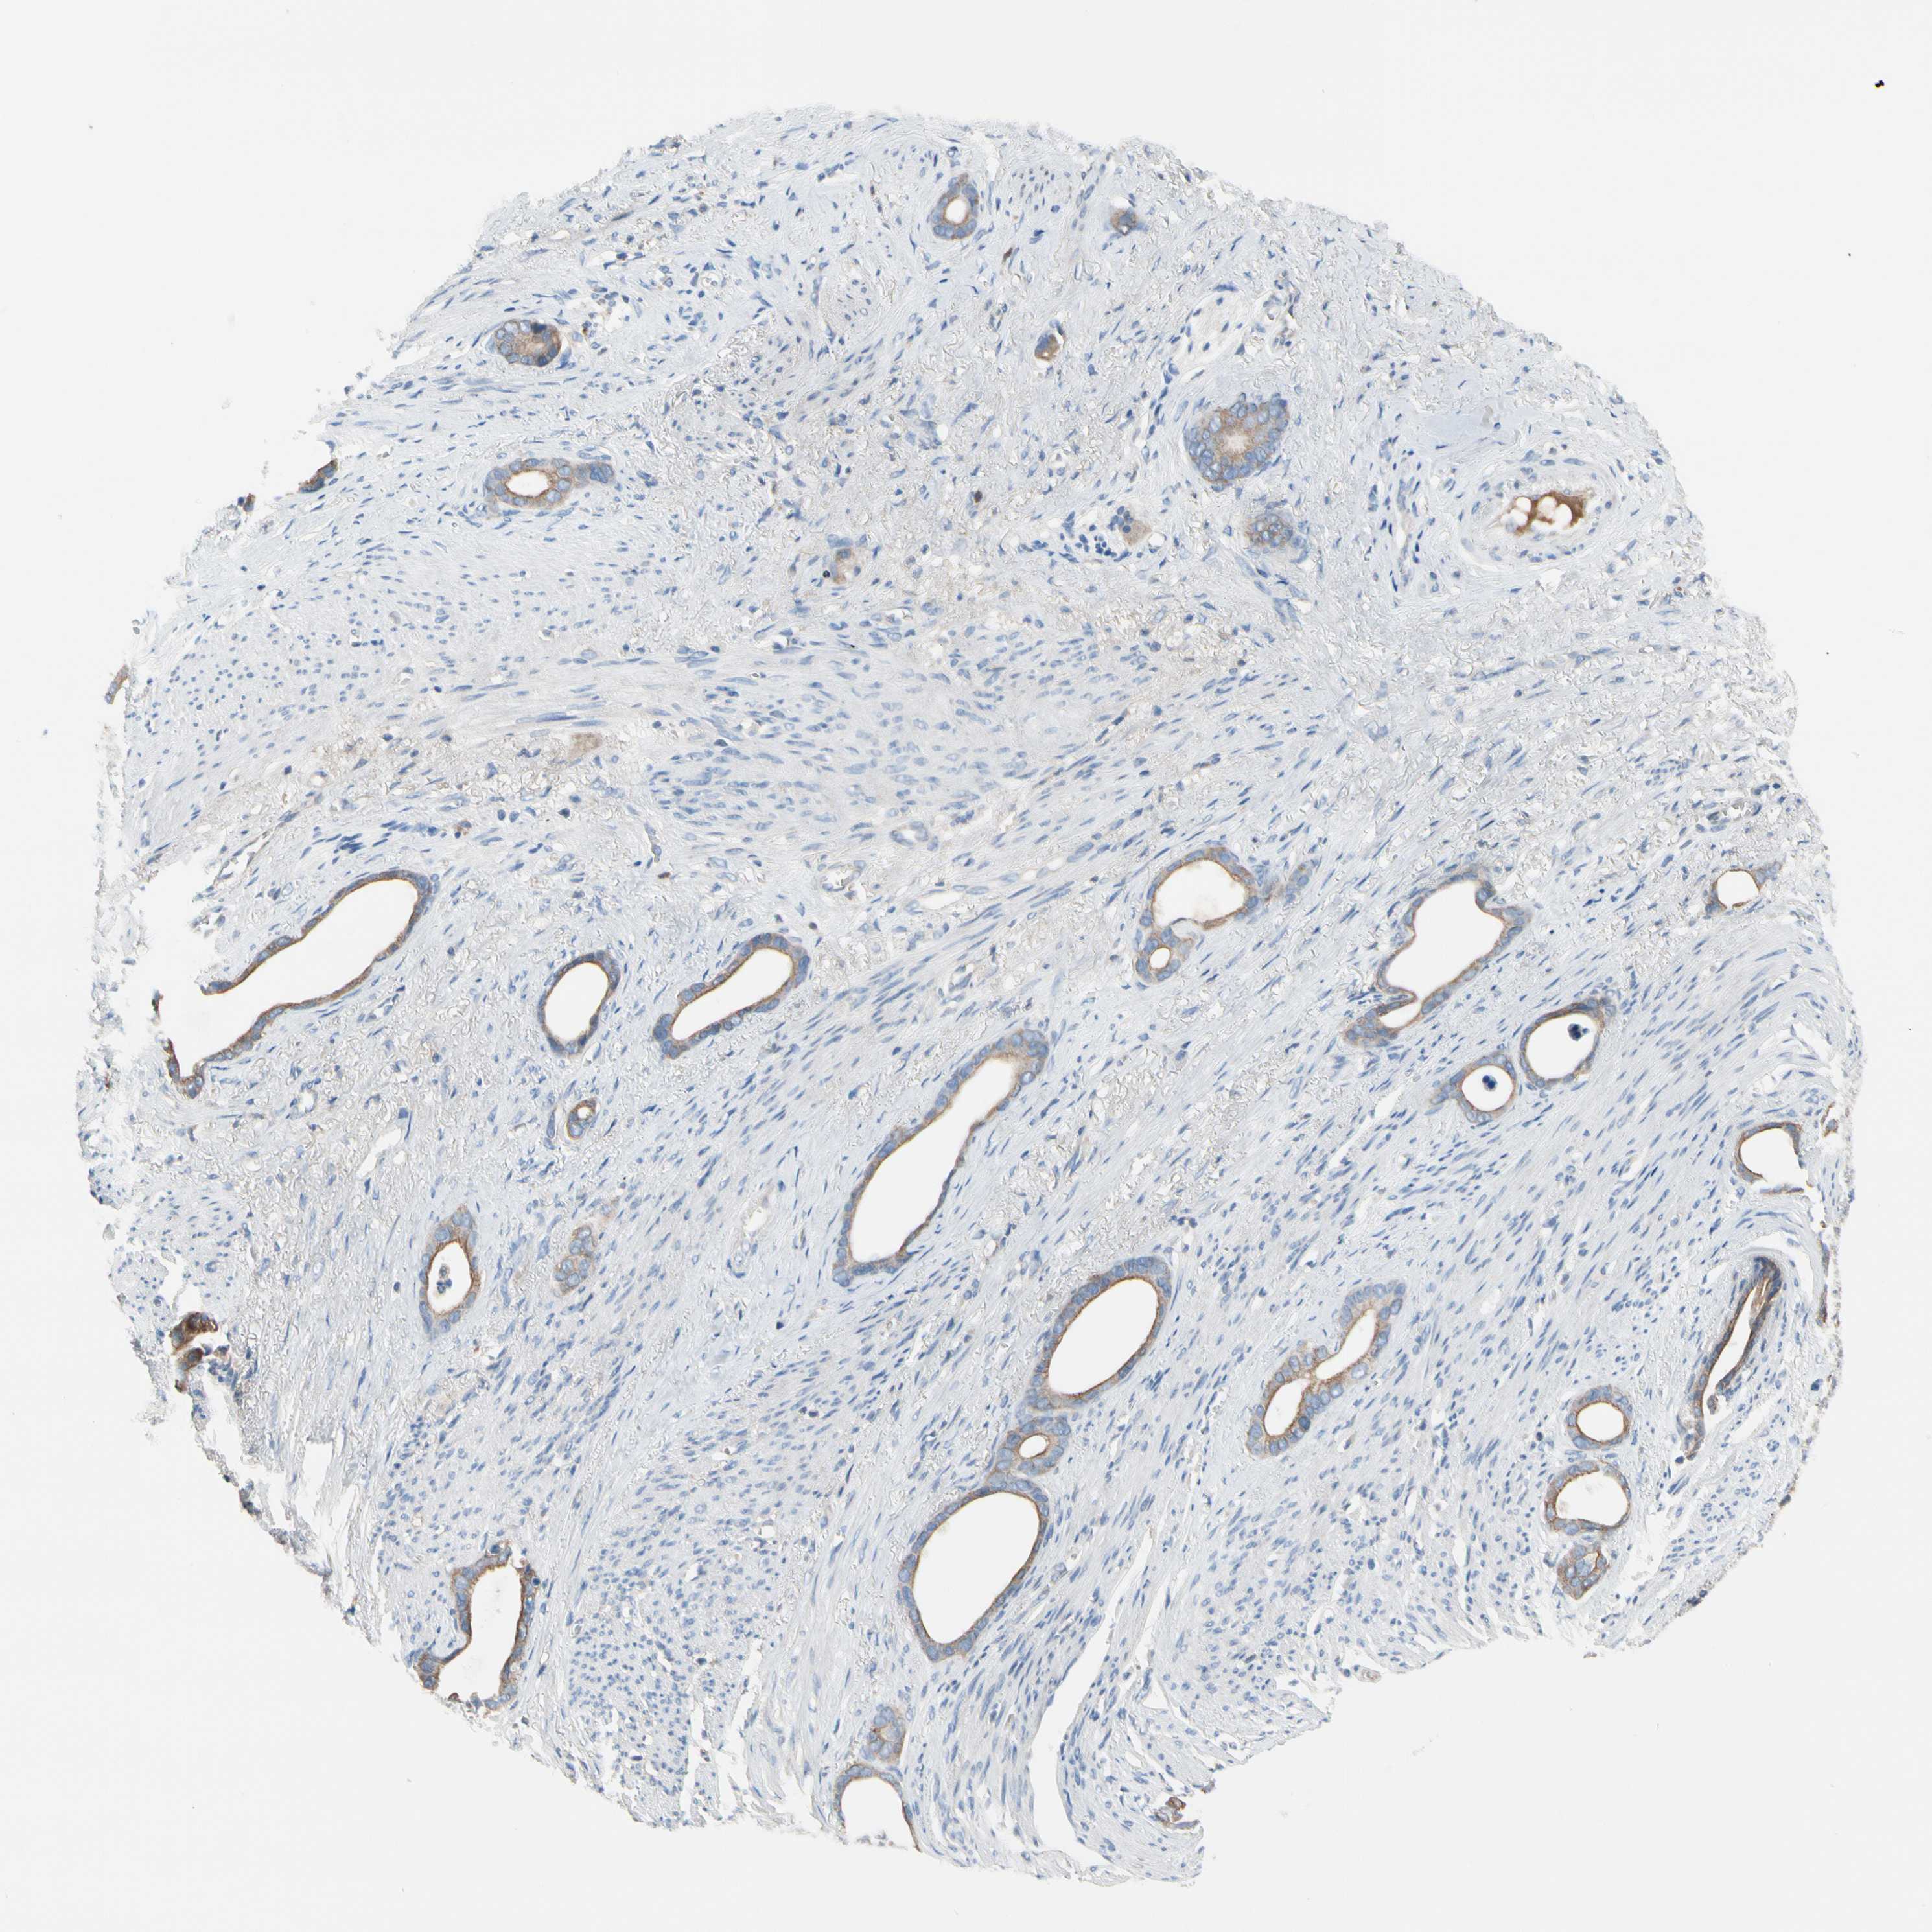

STOMACH CANCER - Protein expressioni

A mouse-over function shows sample information and annotation data. Click on an image to view it in a full screen mode. Samples can be filtered based on level of antibody staining by selecting one or several of the following categories: high, medium, low and not detected. The assay and annotation is described here.

Note that samples used for immunohistochemistry by the Human Protein Atlas do not correspond to samples in the TCGA dataset.

Antibody stainingi

Antibody staining in the annotated cell types in the current human tissue is reported as not detected, low, medium, or high, based on conventional immunohistochemistry profiling in selected tissues. This score is based on the combination of the staining intensity and fraction of stained cells.

Each image is clickable and will lead to virtual microscopy that enables deeper exploration of all samples and also displays staining intensity scores, fraction scores and subcellular localization as well as patient and tissue information for each sample.

Antibody HPA008436

Staining

High

Medium

Low

Not detected

Intensity

Strong

Moderate

Weak

Negative

Quantity

>75%

75%-25%

<25%

None

Location

Nuclear

Cytoplasmic/membranous

Cytoplasmic/membranous,nuclear

Adenocarcinoma, NOS